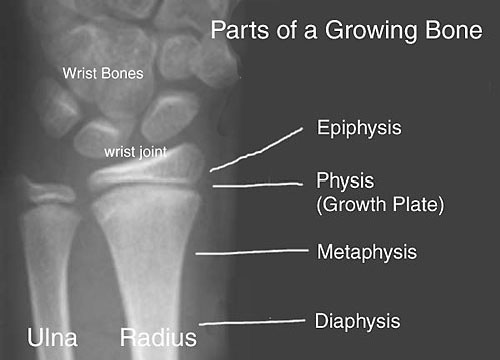

What is the physis in pediatric bones?

The cartilaginous growth plate between the diaphysis and epiphysis.

Before complete ossification, at the growth plates.

They are weaker due to immature ossification.